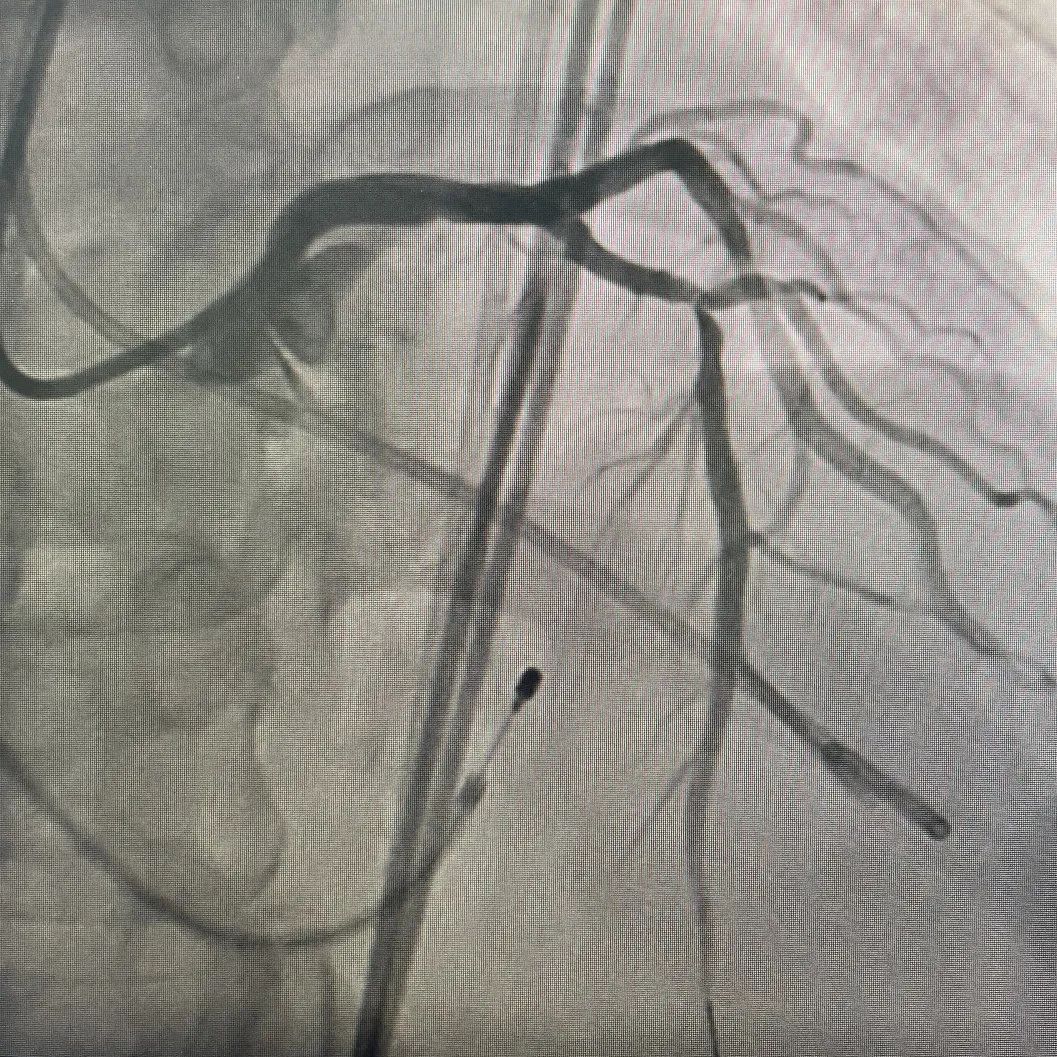

术中操作

冠脉处理前

冠脉处理后

冠脉处理前后对比

球囊扩张

瓣膜释放